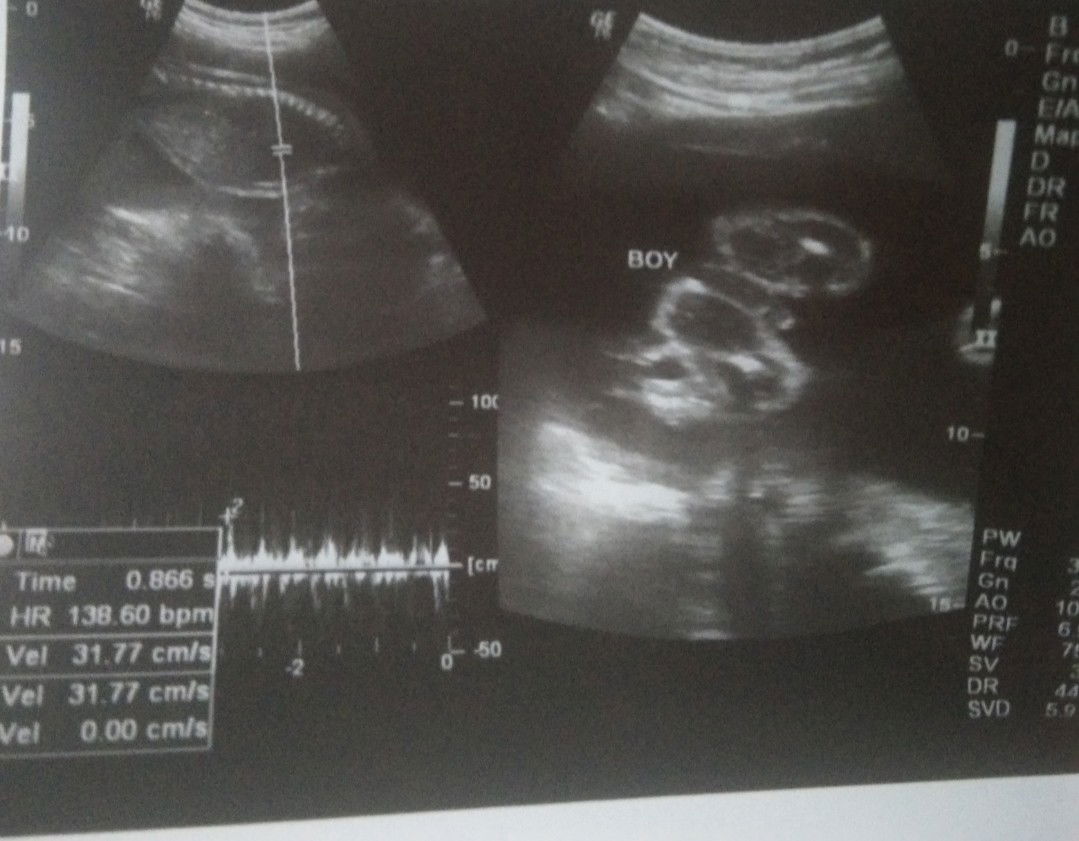

share ko lang po nag paultrasound kami kanina and super happy lang na baby boy po siya ๐ malakas talaga kutob ko noon pa hehe